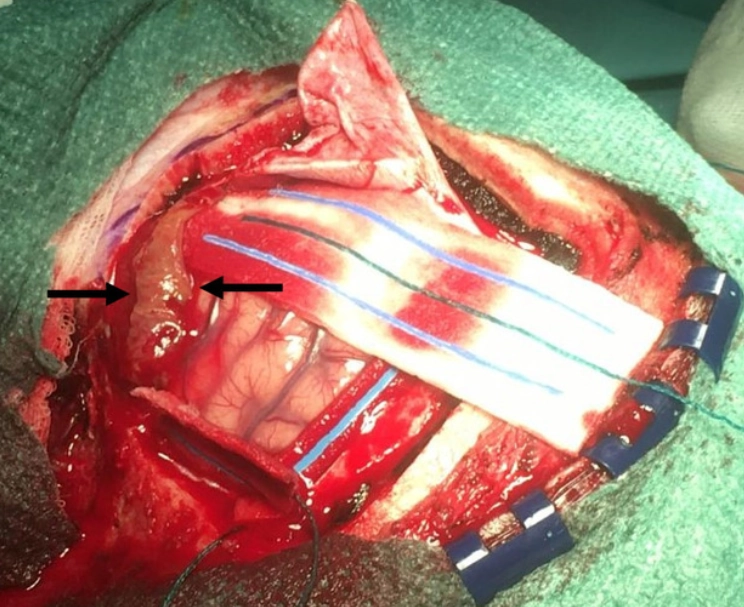

U lympho hệ thần kinh trung ương (Central Nervous System Lymphoma - CNS Lymphoma)